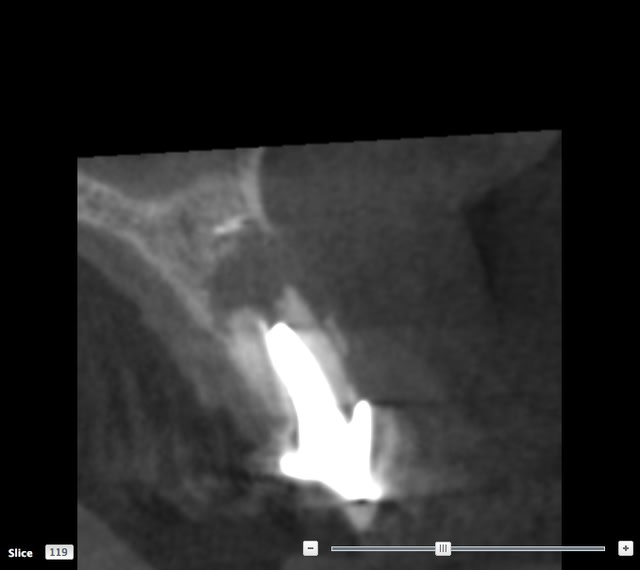

SCAN

Il y a 3.6 mm d'os au dessus du granulome